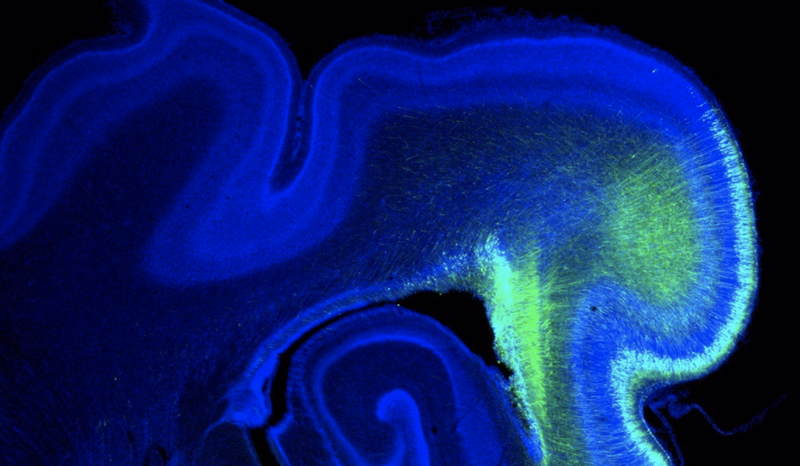

Imagen del cerebro de un hurón. - IN (CSIC-UMH)

Este microARN (miARNs) denominado MIR3607, que se activa durante el desarrollo embrionario, es el responsable del tamaño del cerebro en especies como el hurón o el ser humano. Este estudio, publicado en la revista 'Science Advances', muestra la importancia de los miARNS en la evolución de los mamíferos, ya que su inactividad en los ratones deriva en cerebros pequeños y lisos.

"Los mecanismos genéticos que subyacen a esta pérdida secundaria en la evolución del cerebro de los roedores eran completamente desconocidos hasta ahora. Con nuestro trabajo mostramos que el microARN MIR3607 se expresa embrionariamente en la gran corteza cerebral de los primates y carnívoros, como el hurón; pero no en el ratón", explica Víctor Borrell, investigador del IN (CSIC-UHM) que ha liderado el estudio.